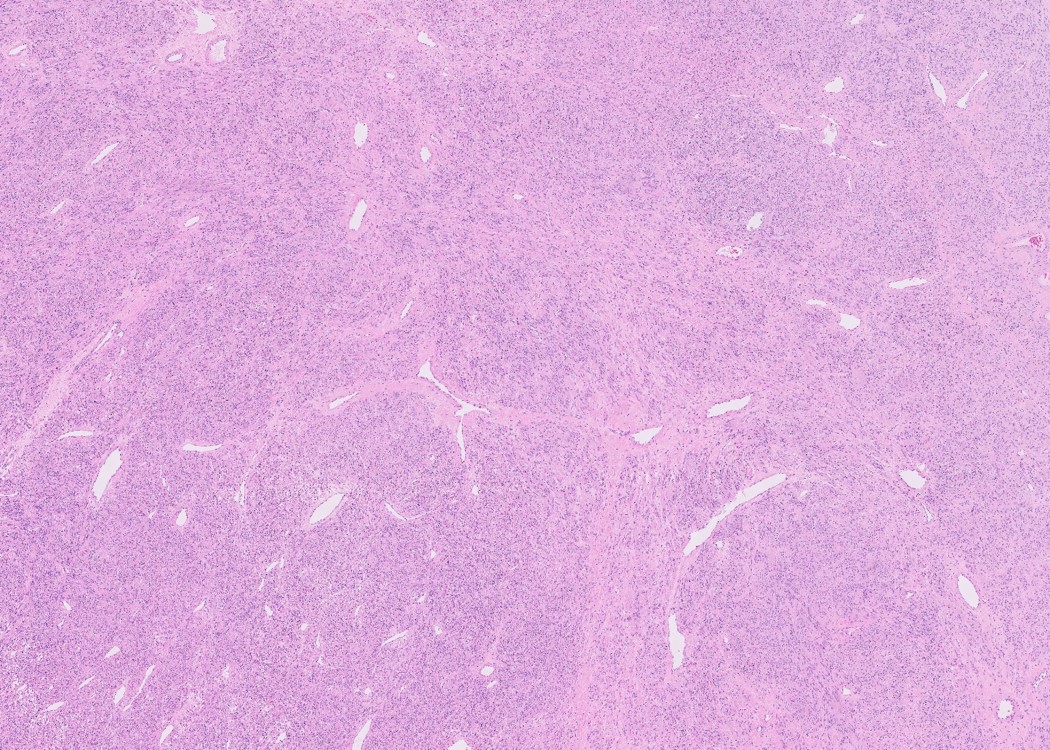

Microscopic (histologic) description

- Subtypes:

- Cellular

- Increased cellularity (more cellular than background myometrium)

- Scant cytoplasm without increased mitotic activity and atypia

- May have irregular borders

- Highly cellular leiomyoma is not a WHO diagnosis

- Cellular

Contributed by Sabrina Croce, M.D., Ph.D., Kristina Doytcheva, M.D., Jennifer A. Bennett, M.D. (Case #508) and @Andrew_Fltv on Twitter